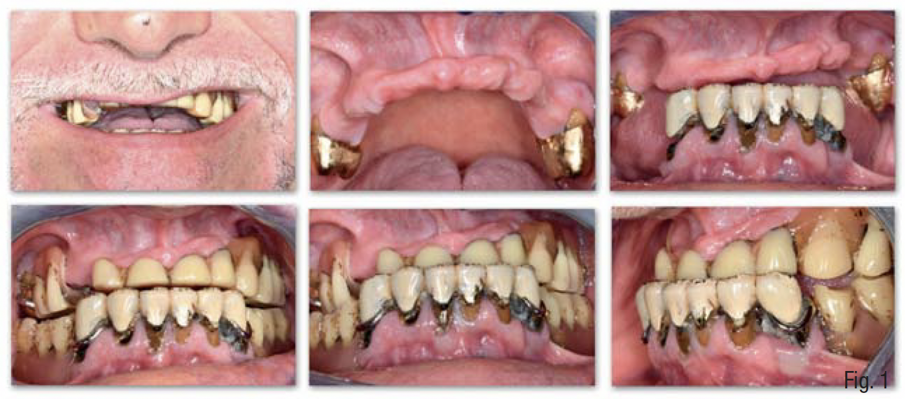

Un paziente di 65 anni, ASA-2, non fumatore è giunto alla nostra osservazione presentando un’edentulia quasi totale del mascellare superiore, con persistenza soltanto dei primi molari 16 e 26 a supporto di una protesi parziale rimovibile, una severa perdita di dimensione verticale occlusale, e una conseguente terza classe acquisita (Fig. 1). La richiesta del paziente era la risoluzione dell’edentulia con protesi fissa supportata da impianti che gli restituisse una funzione e un’estetica ottimale del mascellare superiore ed era già a conoscenza delle problematiche relativa alla mancanza di osso e della necessità di una ricostruzione ossea prima del posizionamento implantare.

Gli esami radiologici di primo livello, quali la OPT, evidenziavano un’altezza ossea sufficiente al posizionamento implantare, ma la successiva analisi di secondo livello, quale la CBCT, evidenziava la presenza di una grave atrofia orizzontale a livello della regione edentula che rendeva impossibile la chirurgia implantare, oltre ad un quadro di sinusite mascellare cronica bilaterale. Su richiesta del paziente, si è deciso di mantenere i 2 molari sup. che sono stati trattati endodonticamente e successivamente protesizzati con 2 corone in zirconia; e di non eseguire il rialzo di seno mascellare bilaterale evitando l’iter terapeutico di approfondimento ORL.